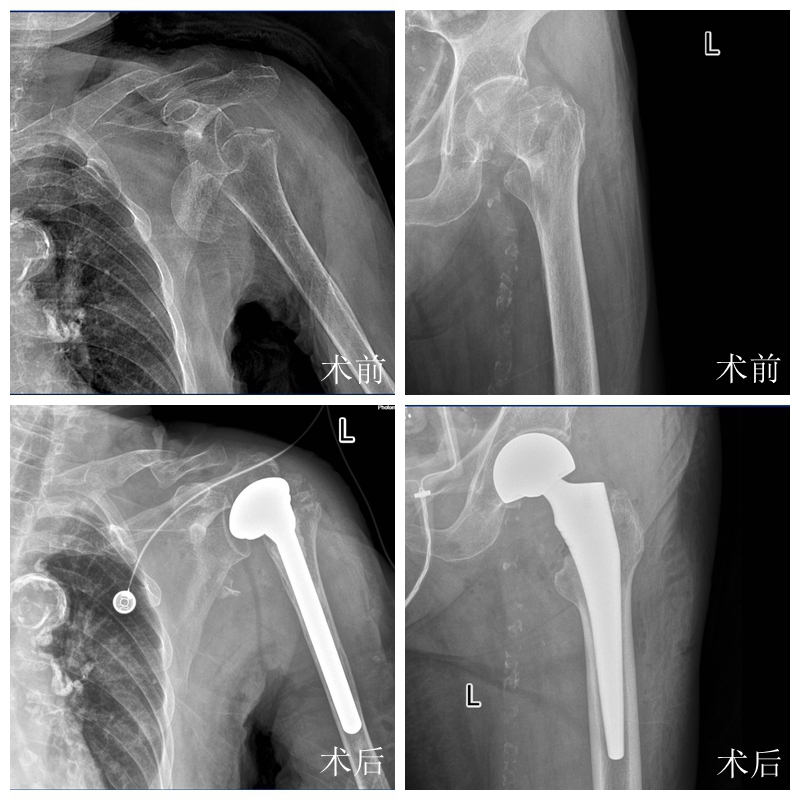

突破高龄手术禁区!95岁阿婆一次置换两关节

从肩关节置换到髋关节置换,两台高难度手术衔接流畅,全程比预期更为平稳,成功为老人重塑了运动功能。

“对高龄患者而言,积极手术往往能避免长期卧床带来的更大风险,实现从‘保命’到‘保生活质量’的转变。”陈文辉主任介绍,这场95岁超高龄双关节同期置换手术的成功,不仅彰显了医院创伤关节外科的综合救治实力,更印证了多学科协作(MDT)模式的优越性,打破了“超高龄+多重基础病=手术禁区”的固有认知。